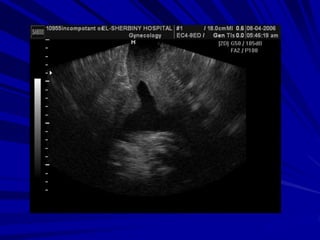

the progressive shortening

detected by serial sonar,

funneling (width and length),

v-shaped lower uterine segment

and dynamic cervical changes

with fundal or suprapubic

pressure.